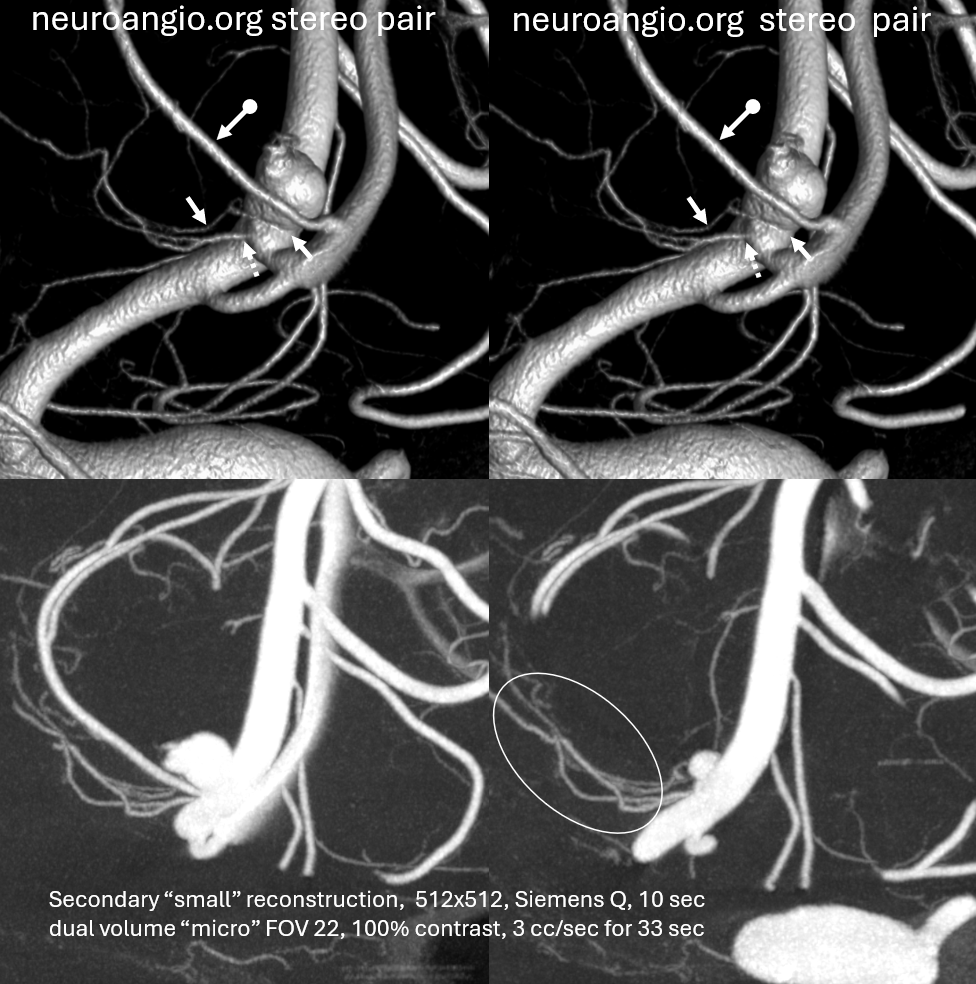

Great case by Vera Sharashidze and Sitara Koneru. Ruptured ACOM. Nothing much to see on 2D DSA — standard issue acom aneurysm, projects posterior…

Volume rendered stereo images of 10 second “micro” FOV 22 dyna Siemens Q — natural fill reconstruction, 3 cc/sec for 33 sec injection. Already better quality than most 3D-DSAs out there

Now we see a subcallosal artery from proximal A2.

Done? of course not. Secondary “small volume” reconstruction. Look at the two hypothalamic perforators — one from acom (dashed arrows), one from aneurysm neck (arrows). Both extremely important, all must be preserved for the sake of hypothalamic function…

Now we know what we need to do. Aneurysm coiled subtotally to ensure neck and acom remain open. Plug and pipe later.